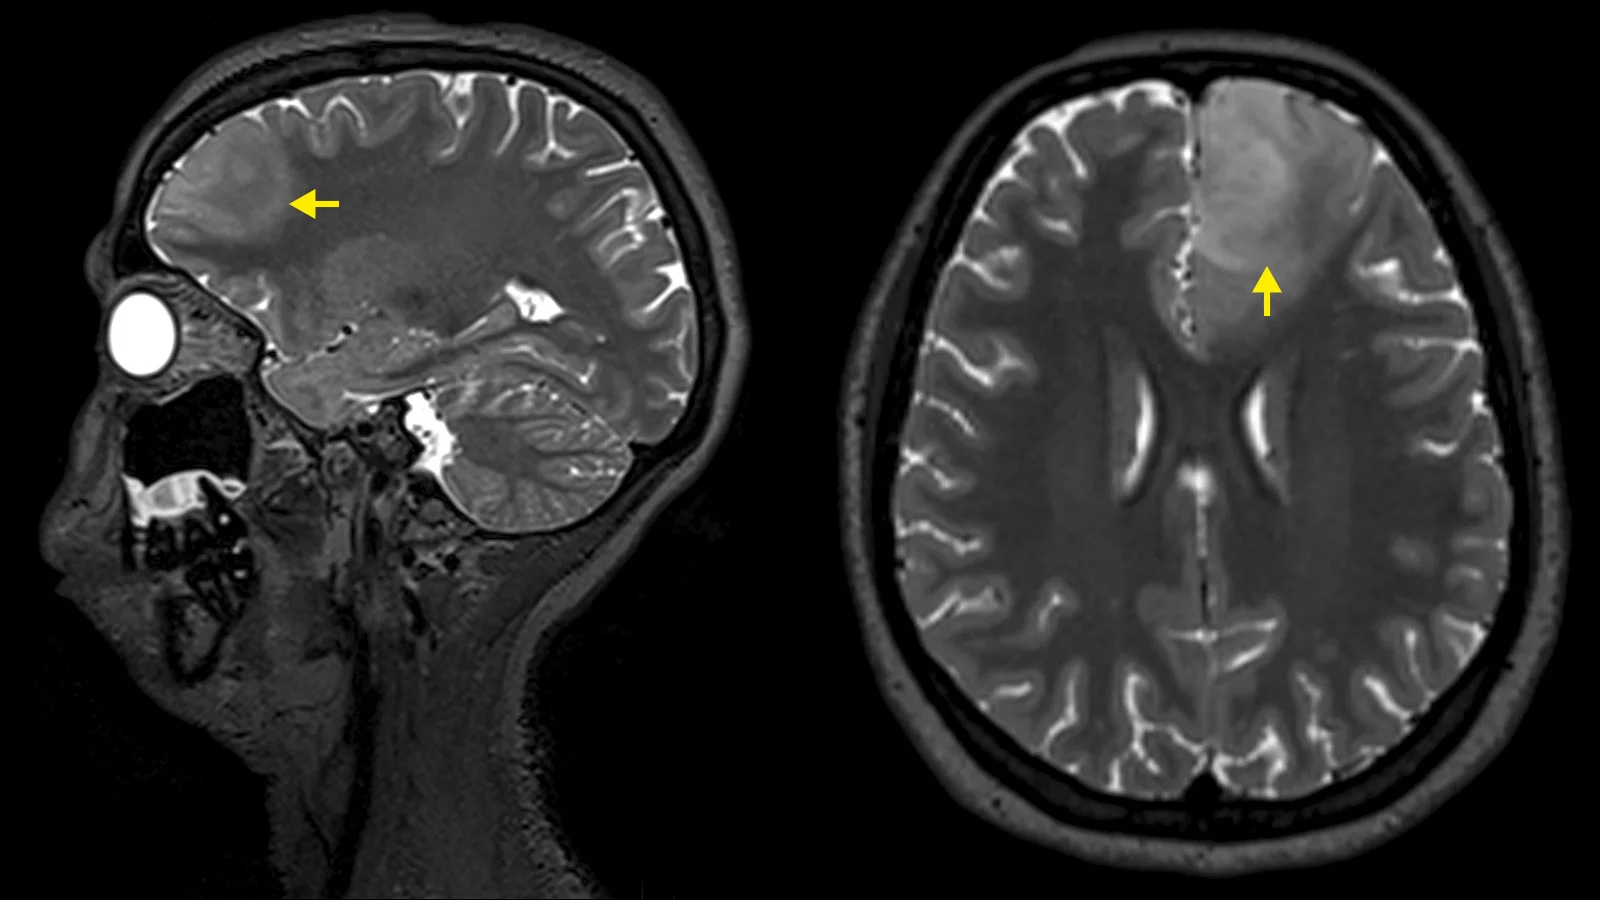

تشخیص آستروسیتوما بر اساس ارزیابی بالینی کامل، یافتههای فیزیکی مشخص، تاریخچه دقیق بیمار و آزمایشهای تخصصی مانند آزمایش خون، تکنیکهای تصویر برداری عصبی و یا سایر مطالعات تشخیصی است. تکنیکهای تصویر برداری عصبی، مانند CT اسکن و تصویر برداری رزونانس مغناطیسی (magnetic resonance imaging یا MRI) مغز به ارزیابی اندازه، محل تومور و سایر عوامل کمک میکنند. در طول سی تی اسکن، از کامپیوتر و اشعه ایکس برای ایجاد تصاویر مقطعی از ساختارهای بافتی خاص استفاده میشود. MRI از یک میدان مغناطیسی برای ایجاد تصاویر مقطعی از اندامها و بافتهای بدن استفاده میکند. بررسی نمونه ای از تومور (بیوپسی) و بررسی میکروسکوپی سلولهای تومور برای تعیین نوع و درجه تومور استفاده میشود.